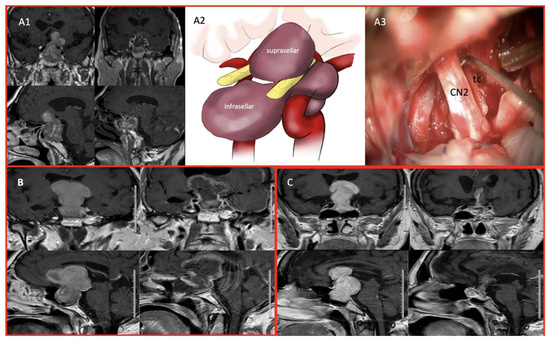

- Yilmaz, E.; Uzuner, A.; Ceylan, E.C.; Yildirim, P.; Duman Ozturk, S.; Emengen, A.; Gokbel, A.; Caklili, M.; Cabuk, B.; Anik, I.; et al. Operative Nuances of Capsular Dissection Techniques and Capsule Morphology in Pituitary Adenomas: Past 1-Year Case Experiences of a Tertiary Center. Oper. Neurosurg. 2024, 27, 681–689. [Google Scholar] [CrossRef]